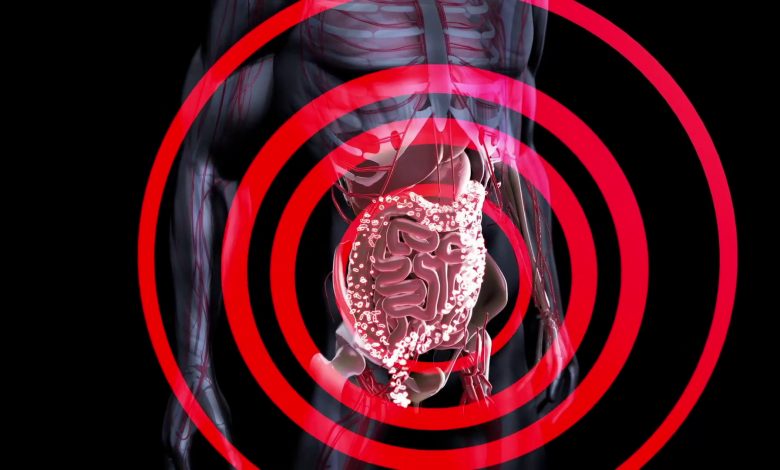

Malattie croniche dell’intestino per 250 mila italiani

ROMA (ITALPRESS) – Oltre 250 mila persone in Italia soffrono di Malattie Infiammatorie Croniche dell’Intestino, Colite Ulcerosa e Malattia di Crohn. Definite come disabilità invisibili, in realtà impattano fortemente sulla quotidianità di chi ne è affetto. La natura cronica di queste condizioni può rendere difficile la pianificazione della propria vita nel lungo termine e se la diagnosi è fatta soprattutto su giovani donne fertili, la malattia incide su aspetti delicati della propria vita come la programmazione di una gravidanza. Tra gli istituti italiani maggiormente specializzati in queste patologie, l’IBD Center di Humanitas che ha recentemente organizzato un’iniziativa di incontro tra medici e pazienti in collaborazione con l’Associazione Nazionale per le Malattie Infiammatorie Croniche dell’Intestino, AMICI Italia.